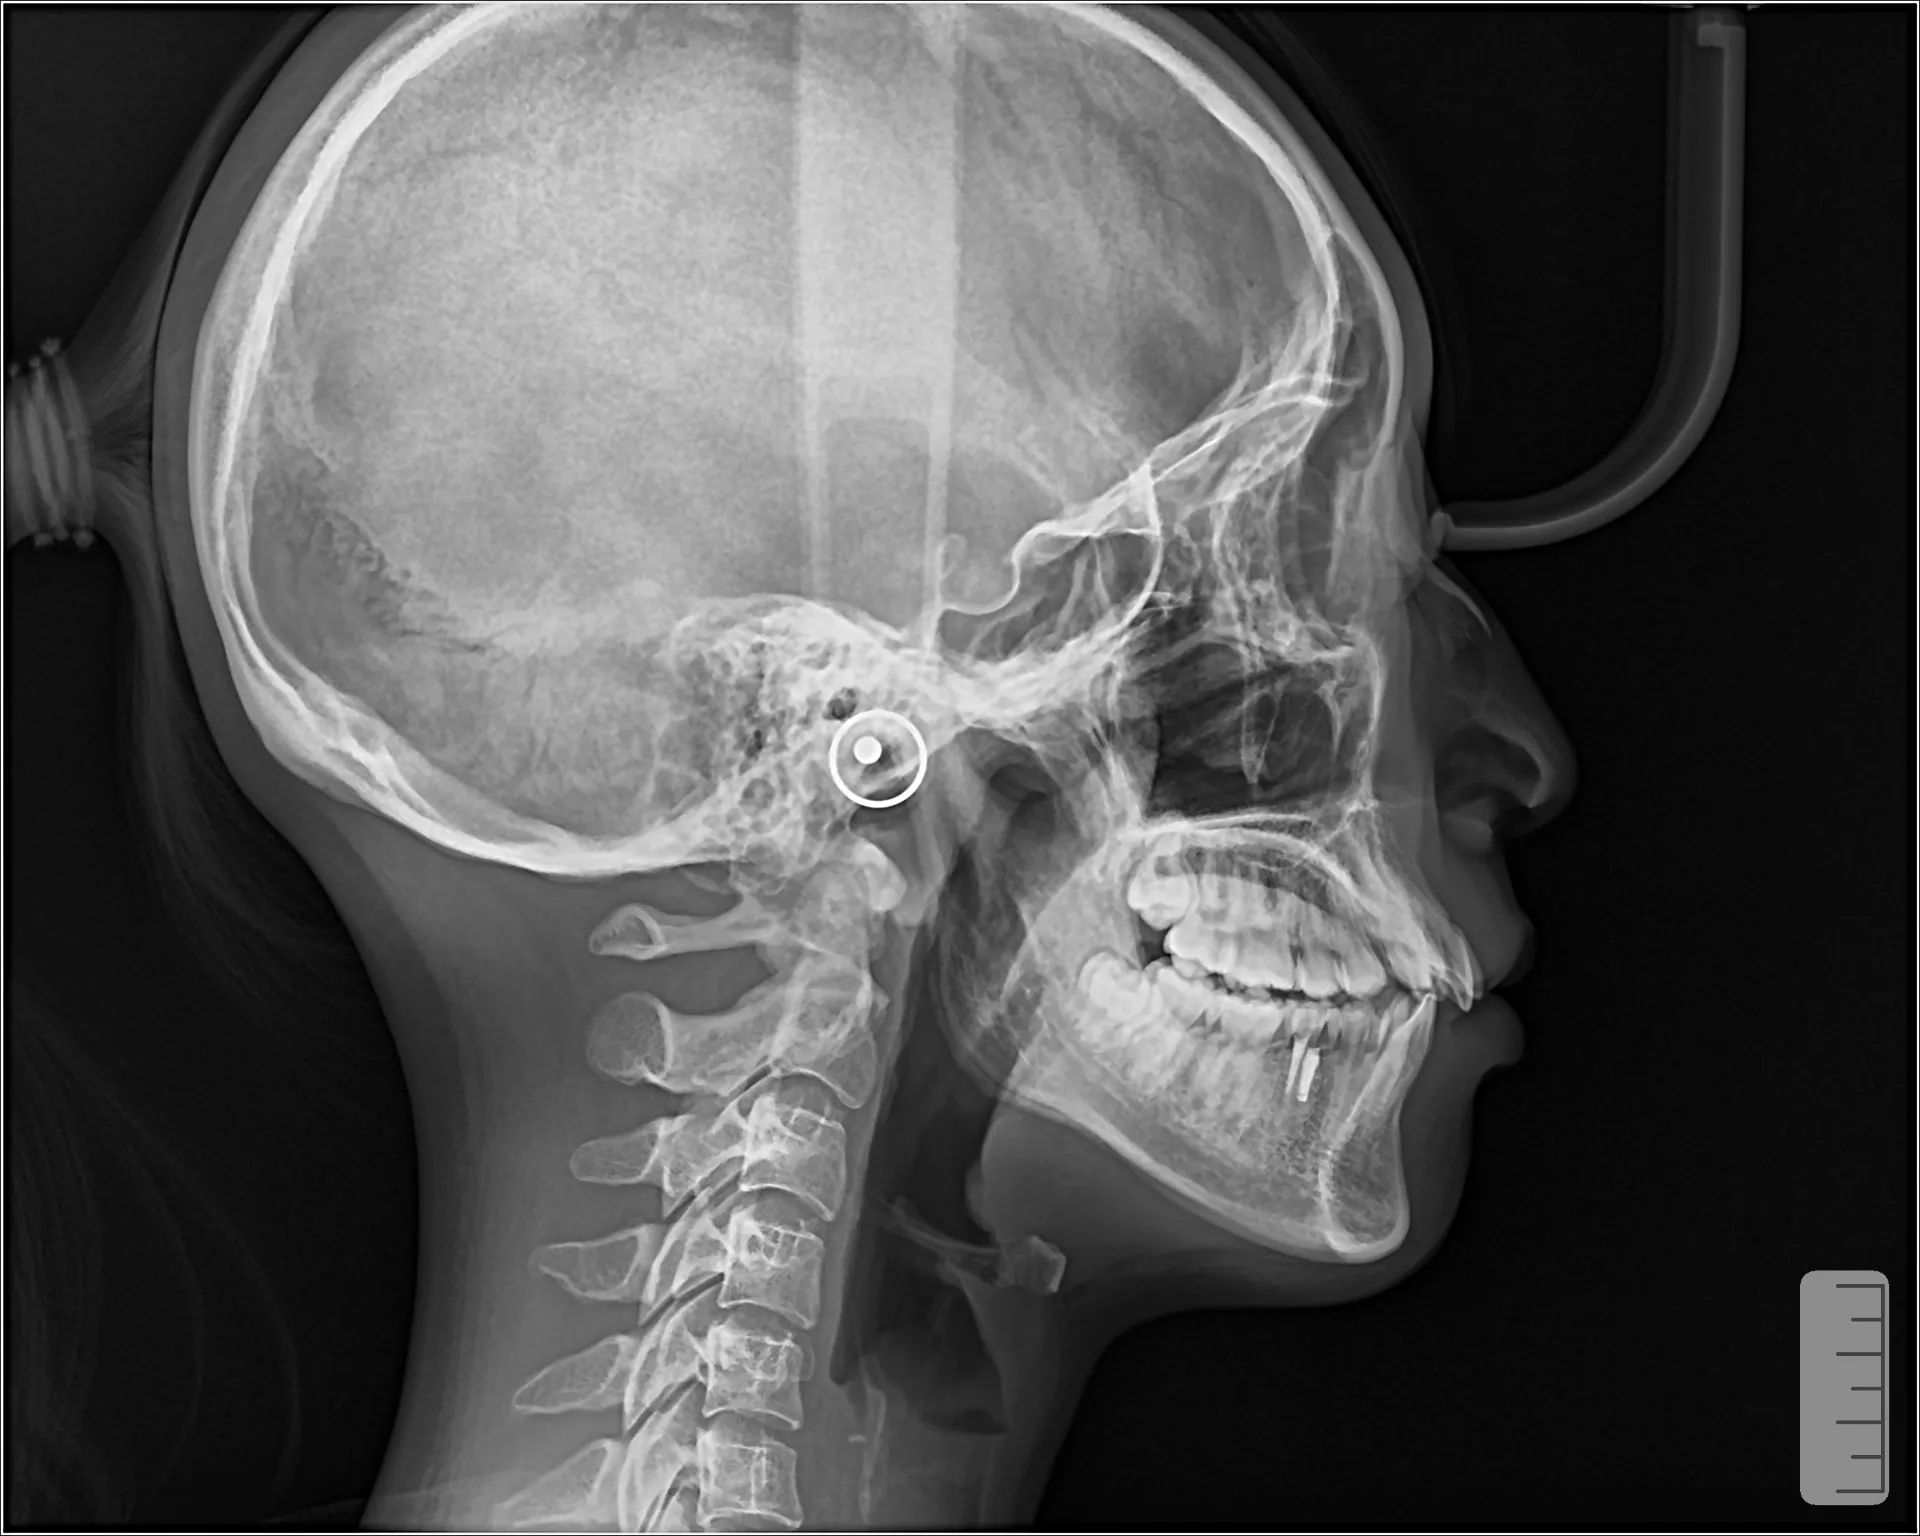

**Eライン(Esthetic Line)**とは、

鼻先と顎先を結んだ直線のことです。

理想的な口元の目安

上唇:Eラインより 約−4mm

下唇:Eラインより 約−2mm

つまり

👉 唇がEラインより少し内側にある状態が美しいとされます。

※ただし日本人は欧米人より口元が出やすいので

Eライン上〜やや前でも自然とされています。